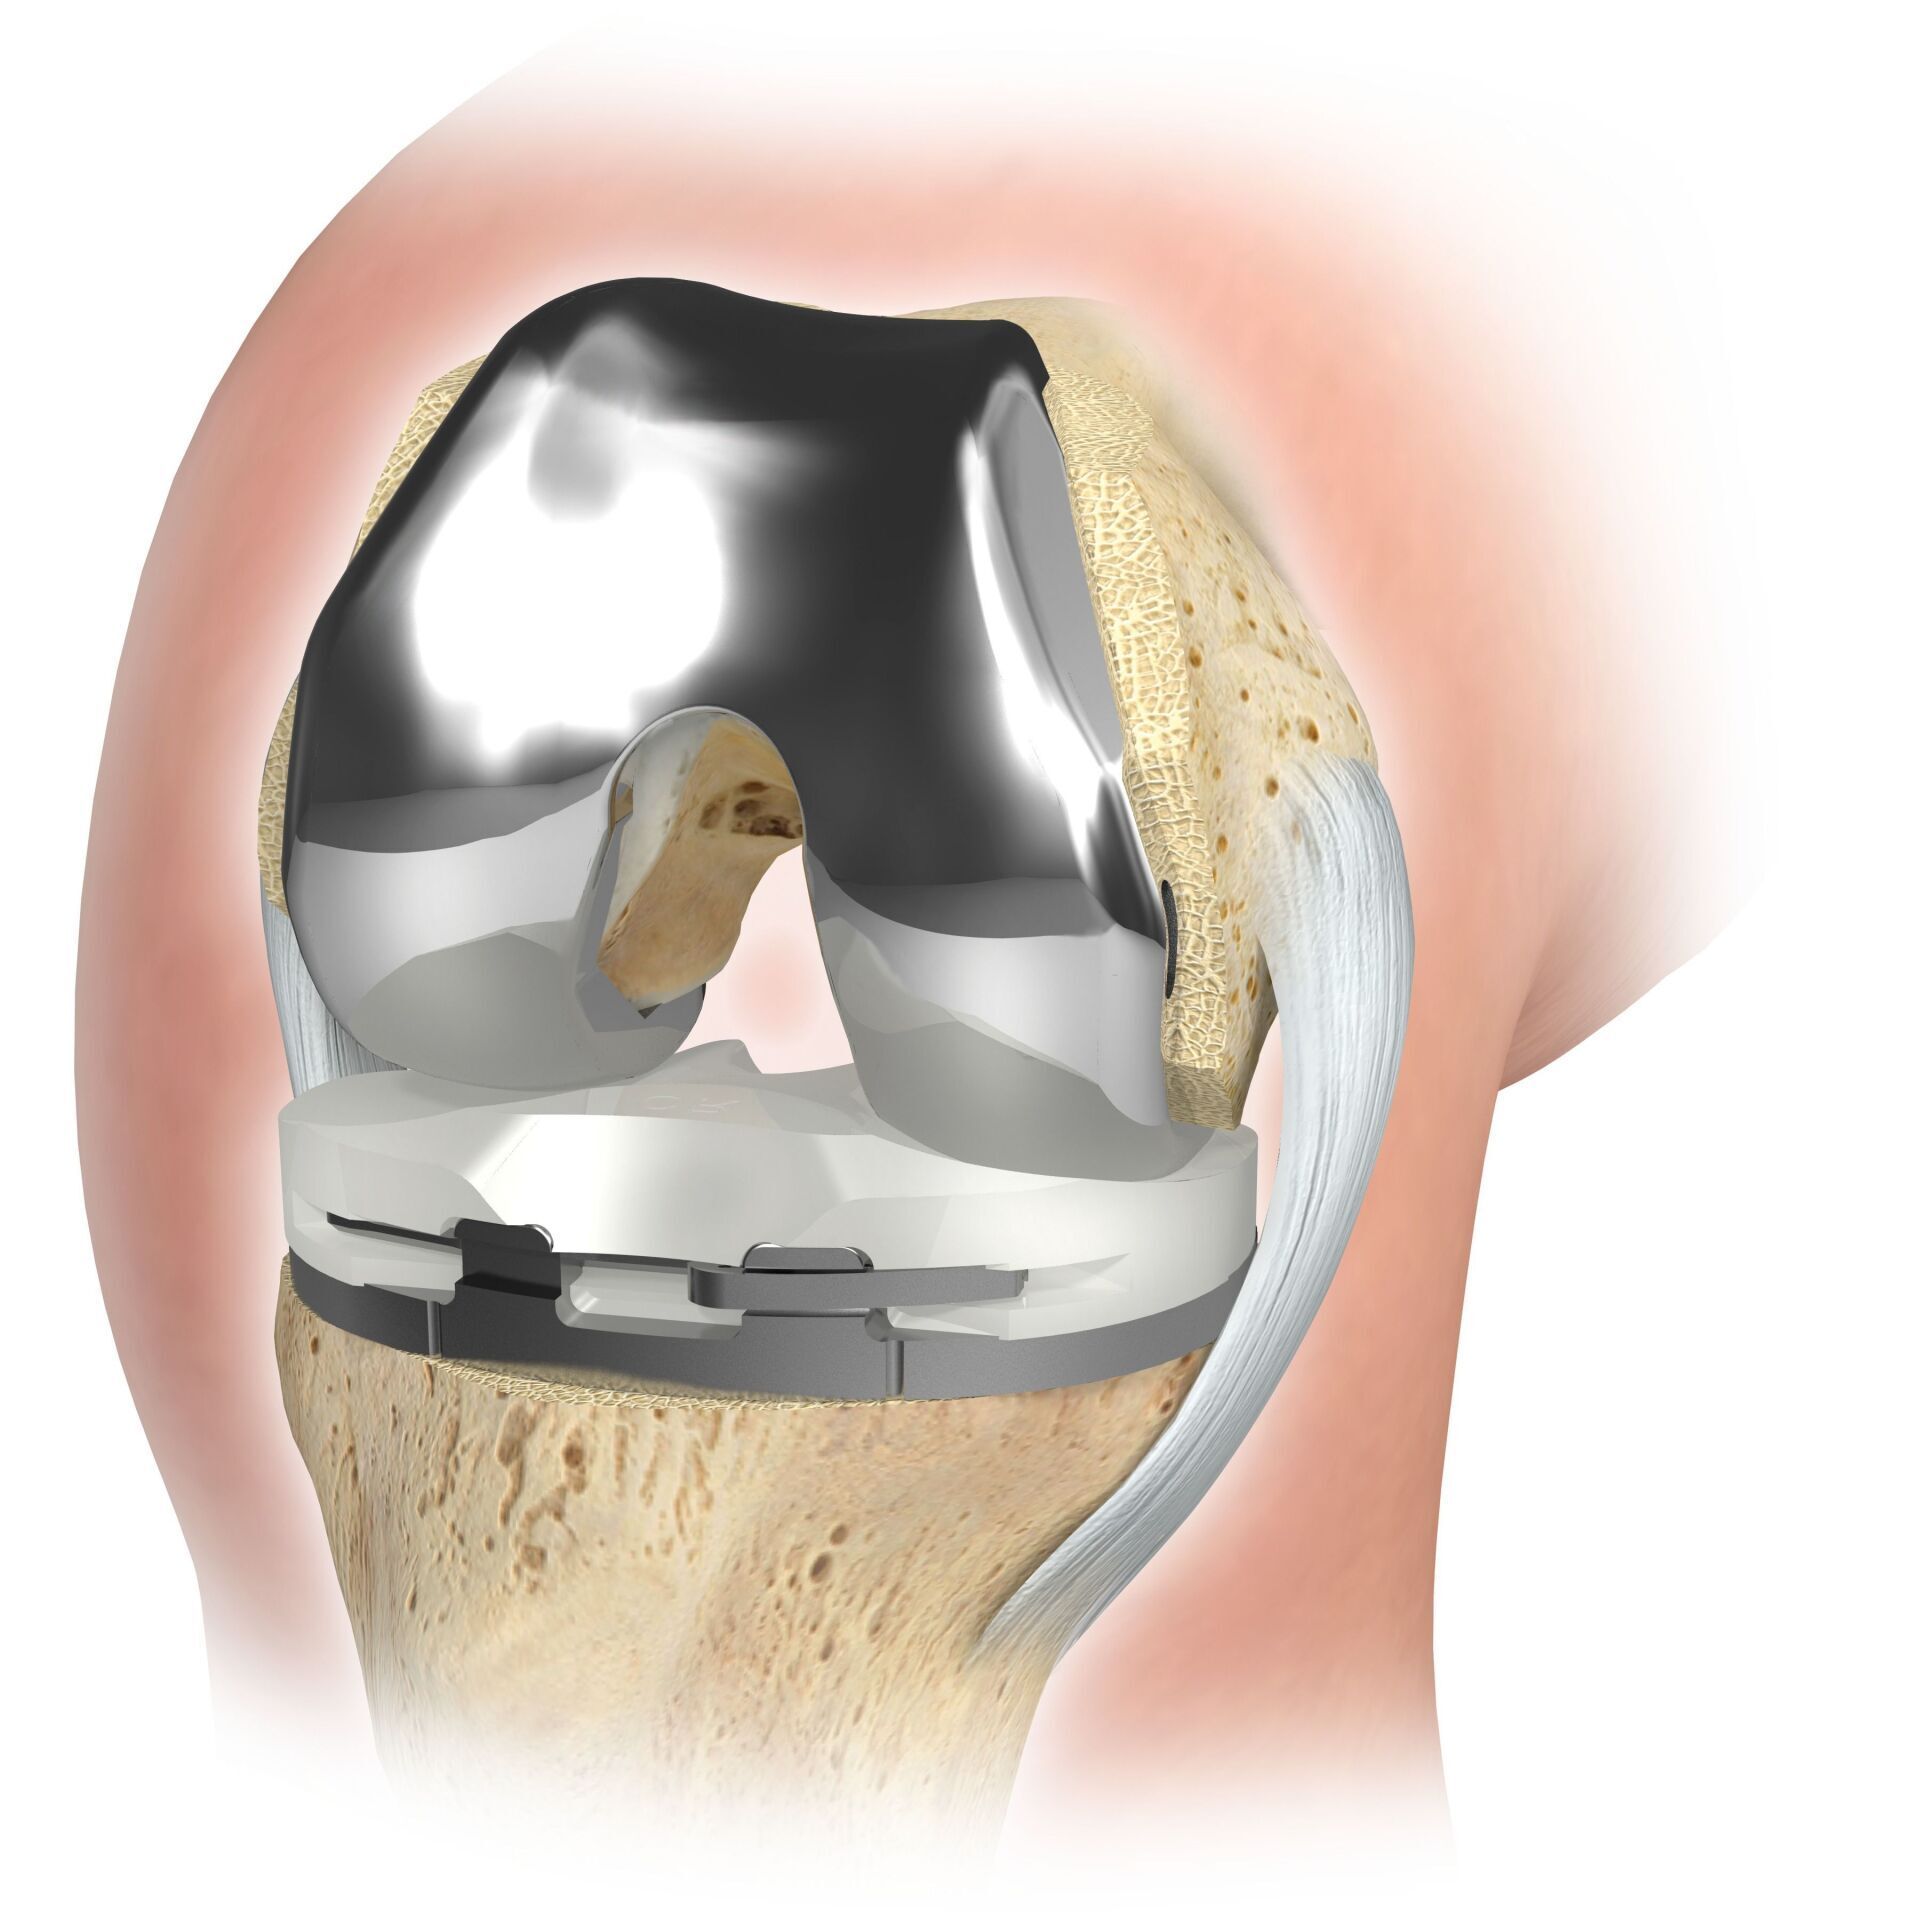

PTG (ARTICULATION ARTIFICIELLE DU GENOU)

L’articulation artificielle du genou remplace la surface cartilagineuse détruite par l’arthrose. L'os sous-jacent du fémur et de la tête tibiale reste intact. Certains comparent une articulation artificielle moderne du genou à un couronnement de dent ; le terme exact est ce qu'on appelle le resurfaçage bicondylien. Entre les nouvelles surfaces sur la partie supérieure et inférieure de la jambe se trouve ce que l'on appelle une incrustation en plastique blanc spécialement durci, qui peut être vue sur l'image radiographique comme la distance entre les pièces métalliques.